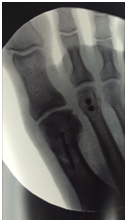

Upon adequate visualization of the plantar plate, a full thickness flap is created to allow for a mattress suture on proximal end of the plantar plate. Next, crossed tunnels are drilled on the proximal phalanx. The suture from the proximal end is passed from plantar to dorsal through the tunnels. Next, fixate the Weil osteotomy with 2 small screws (Figure 6). The sutures are tightened with the phalanx plantarflexed 15-20 degrees and tie sutures. Standard skin closure in layers is performed. The postoperative course is identical to what is described in the plantar approach description above.

Figure 6 Weil metatarsal osteotomy with 2.0 mm screw fixation.